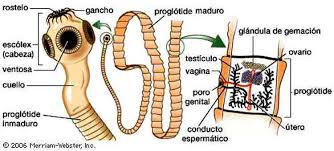

Los parásitos son metazoos pluricelulares y complejos. Alguno de ellos son insectos (piojos, pulgas), arácnidos (ácaros de la sarna, garrapatas), cestones (gusanos chatos o tenias) y nematodos (gusanos redondos). Ciertas parasitosis internas son enfermedades ocasionadas por gusanos, que afectan a varios sistemas como el digestivo o el respiratorio. Ingresan por vía oral a través del agua o los alimentos infestados de huevos o larvas del parásito, como sucede con las ascaridiasis, la oxiuriasis y la teniasis. La sarna y la pediculosis son parasitosis externas, provocadas por un ácaro y por un insecto, respectivamente.

ENFERMEDADES PARASITARIAS

Son provocadas por parásitos que se alojan dentro del organismo (tenias y gusanos el intestino) o sobre la superficie del cuerpo (sarna, piojos), con lo cual puede clasificárselas en parasitosis internas o externas, respectivamente. Un parásito es un organismo que vive y se nutre a expensas de otro organismo (hospedador), ocasionándole diversos trastornos en la salud. Las manifestaciones clínicas pueden estar ausentes (portadores asintomáticos), presentar formas leves o una severa sintomatología, dependiendo esto de las defensas del hospedador, de la toxicidad de la noxa presente y de la cantidad de parásitos que afecten al individuo. Los parásitos son eucariotas uni y pluricelulares de estructura compleja. Se clasifican en:

-Protozoos

-Metazoos: Helmintos (platelmintos y nematelmintos)

-Artrópodos (insectos y ácaros)

La vía de transmisión de los parásitos puede ser directa entre personas o animales (escabiosis, pediculosis), vía transplacentaria (toxoplasmosis), a través del agua o los alimentos (ascaridiasis, teniasis), de los suelos contaminados o por medio de vectores artrópodos (mal de Chagas, paludismo). La puerta de entrada de los agentes es la digestiva (oral), la respiratoria, la piel y las mucosas.

La prevención antiparasitaria se orienta al control de los reservorios, a las buenas prácticas de higiene personal y de las viviendas, al lavado apropiado de los alimentos y al control de vectores.